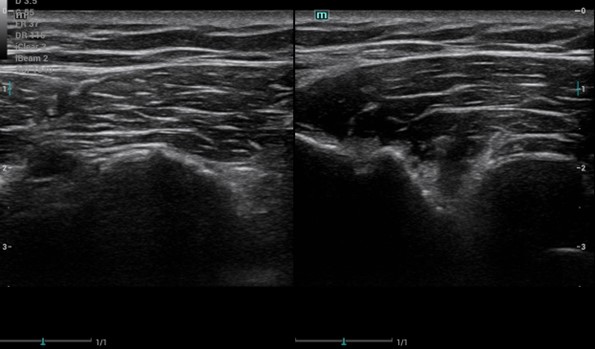

A través de varios casos clínicos se ha hecho una experiencia formativa en el C. Salud tras revisión de la literatura al respecto, se hace una sesión clínica teórica con los distintos diagnósticos diferenciales y hallazgos ecográficos y otra práctica para mostrar cómo explorar la pared torácica. Entre los casos atendidos encontramos: 3 costocondritis, una contusión pulmonar, fractura de esternón a los 15 días tras accidente tráfico, diagnóstico diferencial costocondritis vs metástasis pulmonar en paciente con cáncer de mama, varios casos de artritis de la articulación esternoclavicular, fracturas costales, seromas, hematomas, diagnóstico diferencial con linfomas, abscesos, etc.

El dolor de la pared costal supone uno de los retos más desafiantes en nuestras consultas, debido a que las causas isquémicas como las no isquémicas comparten clínica y síntomas. La ecografía clínica se posiciona como una herramienta clave para mejorar el diagnóstico diferencial del dolor torácico tanto en centro de salud como en las urgencias hospitalarias, por ser inocua, accesible y en el momento de la exploración.